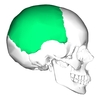

3

Q

A

parietal bone